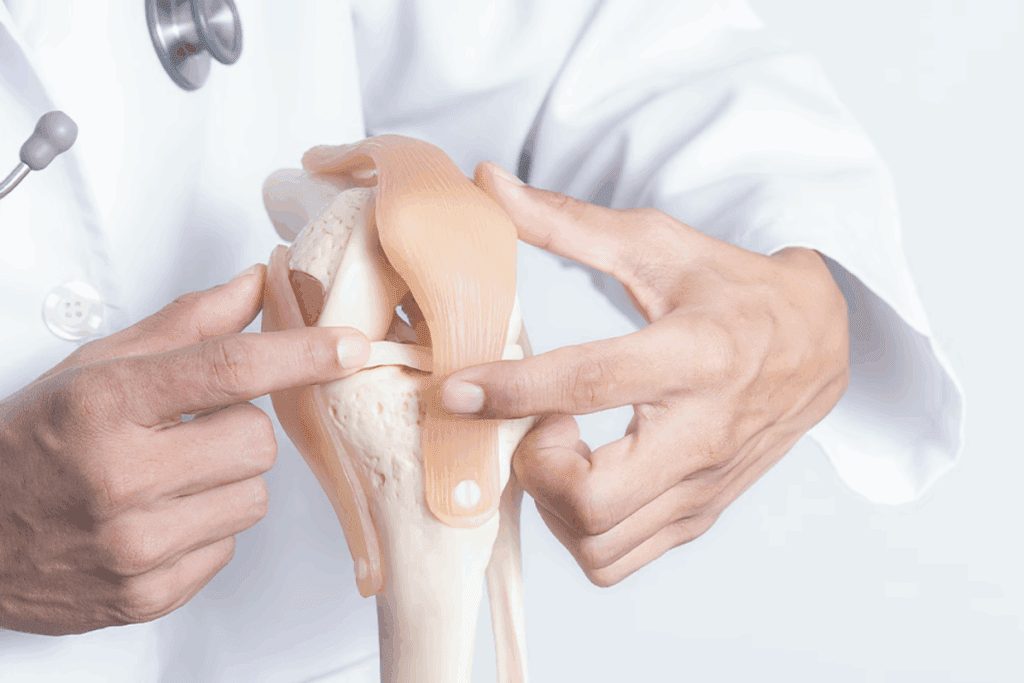

Hinge joints move in one direction, like a door opening. The elbow joint and knee joint are examples. They let us bend and straighten our arms and legs.

These parts work together to support our joints. For example, in the knee, ligaments keep it stable, tendons connect muscles to bones, and muscles help us bend and straighten.

Joint replacement is a big deal for badly damaged joints, like hips and knees. It depends on health, damage, and life quality. We weigh the pros and cons for each patient.